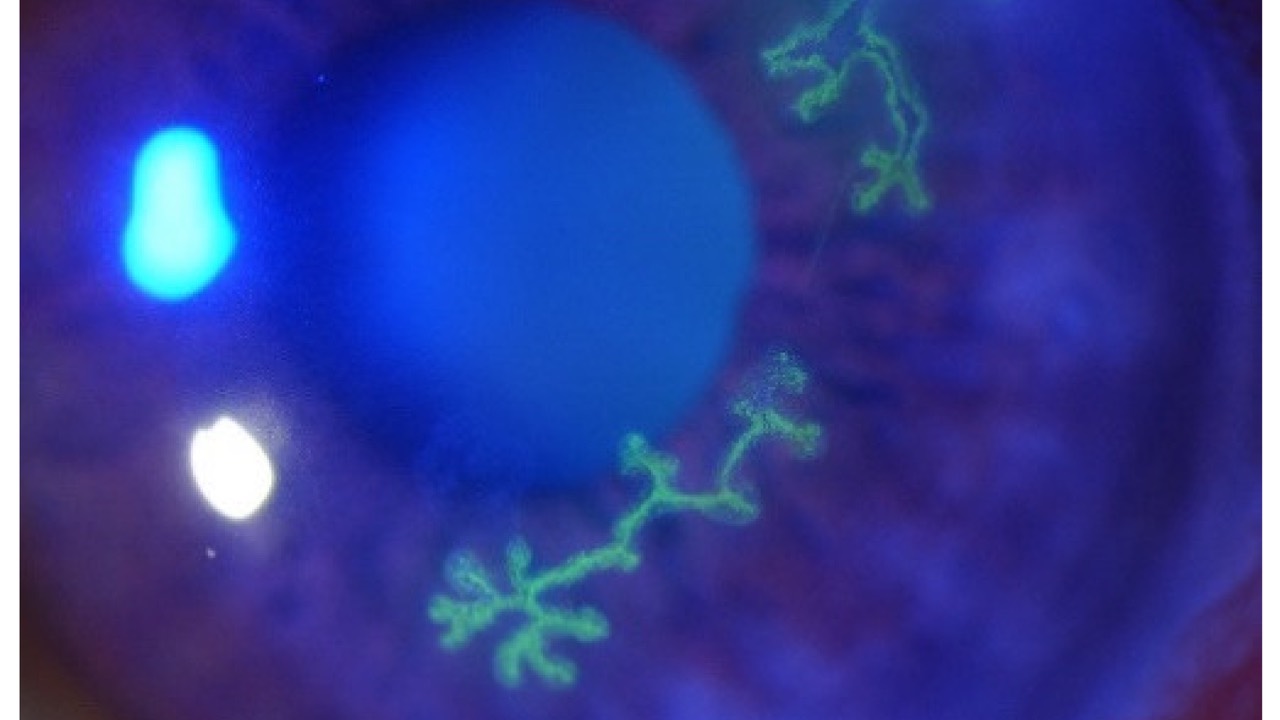

A recent case control study looking at rates of glaucomatous visual field progression before and after the onset of atrial fibrillation found important outcomes for us to consider.

Longitudinal results and meta-analyses found a significant change in visual fields following a diagnosis of atrial fibrillation. The increased progression rates post-onset are most likely linked to micro-thrombi leading to compromised ocular perfusion and ischemia. Additional risk factors include older age, hypertension, and diabetes.

These findings have important clinical implications for us, suggesting early detection and management of atrial fibrillation may help preserve visual function with our glaucoma patients. Perhaps more frequent visual field testing and OCT imaging is now justified, including our glaucoma suspects. We are also reminded of the importance to provide a multidisciplinary approach when managing individuals with or at risk of atrial fibrillation.